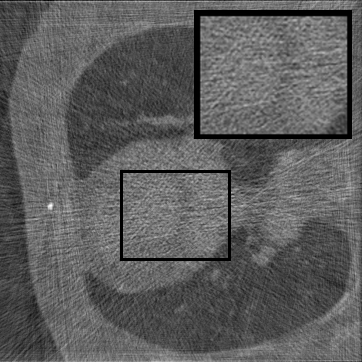

Figure 3: Qualitative completion results on TomoBank (lines 1 to 2) and LoDoPaB (lines 3 to 4) with random mask (ratio = 0.8) at 1024×\times1024 resolution. Odd columns and even columns show the sinograms and reconstructed images, respectively.

Tab 2 summarizes accuracy results. At 2048×\times2048 resolution, HRSino achieves the best performance among all baselines while remaining memory-efficient, demonstrating its ability to extend high-quality completion to resolutions where other diffusion models fail. At 1024×\times1024, HRSino delivers accuracy comparable to its computation-intensive counterpart RePaint, showing that our optimizations do not compromise fidelity at moderate scales. Compared to DiffIR, MCG, TD-Paint, and HiDiffusion, HRSino consistently achieves higher SSIM and PSNR across mask ratios, with improvements up to +0.03 SSIM and +1.8 dB PSNR. Fig 3 visualizes sinogram completion and reconstructed images, where HRSino produces nearly indistinguishable results from RePaint. These findings confirm that HRSino fundamentally extends diffusion-based completion to 2048×\times2048 resolution in a more memory- and runtime-efficient manner.